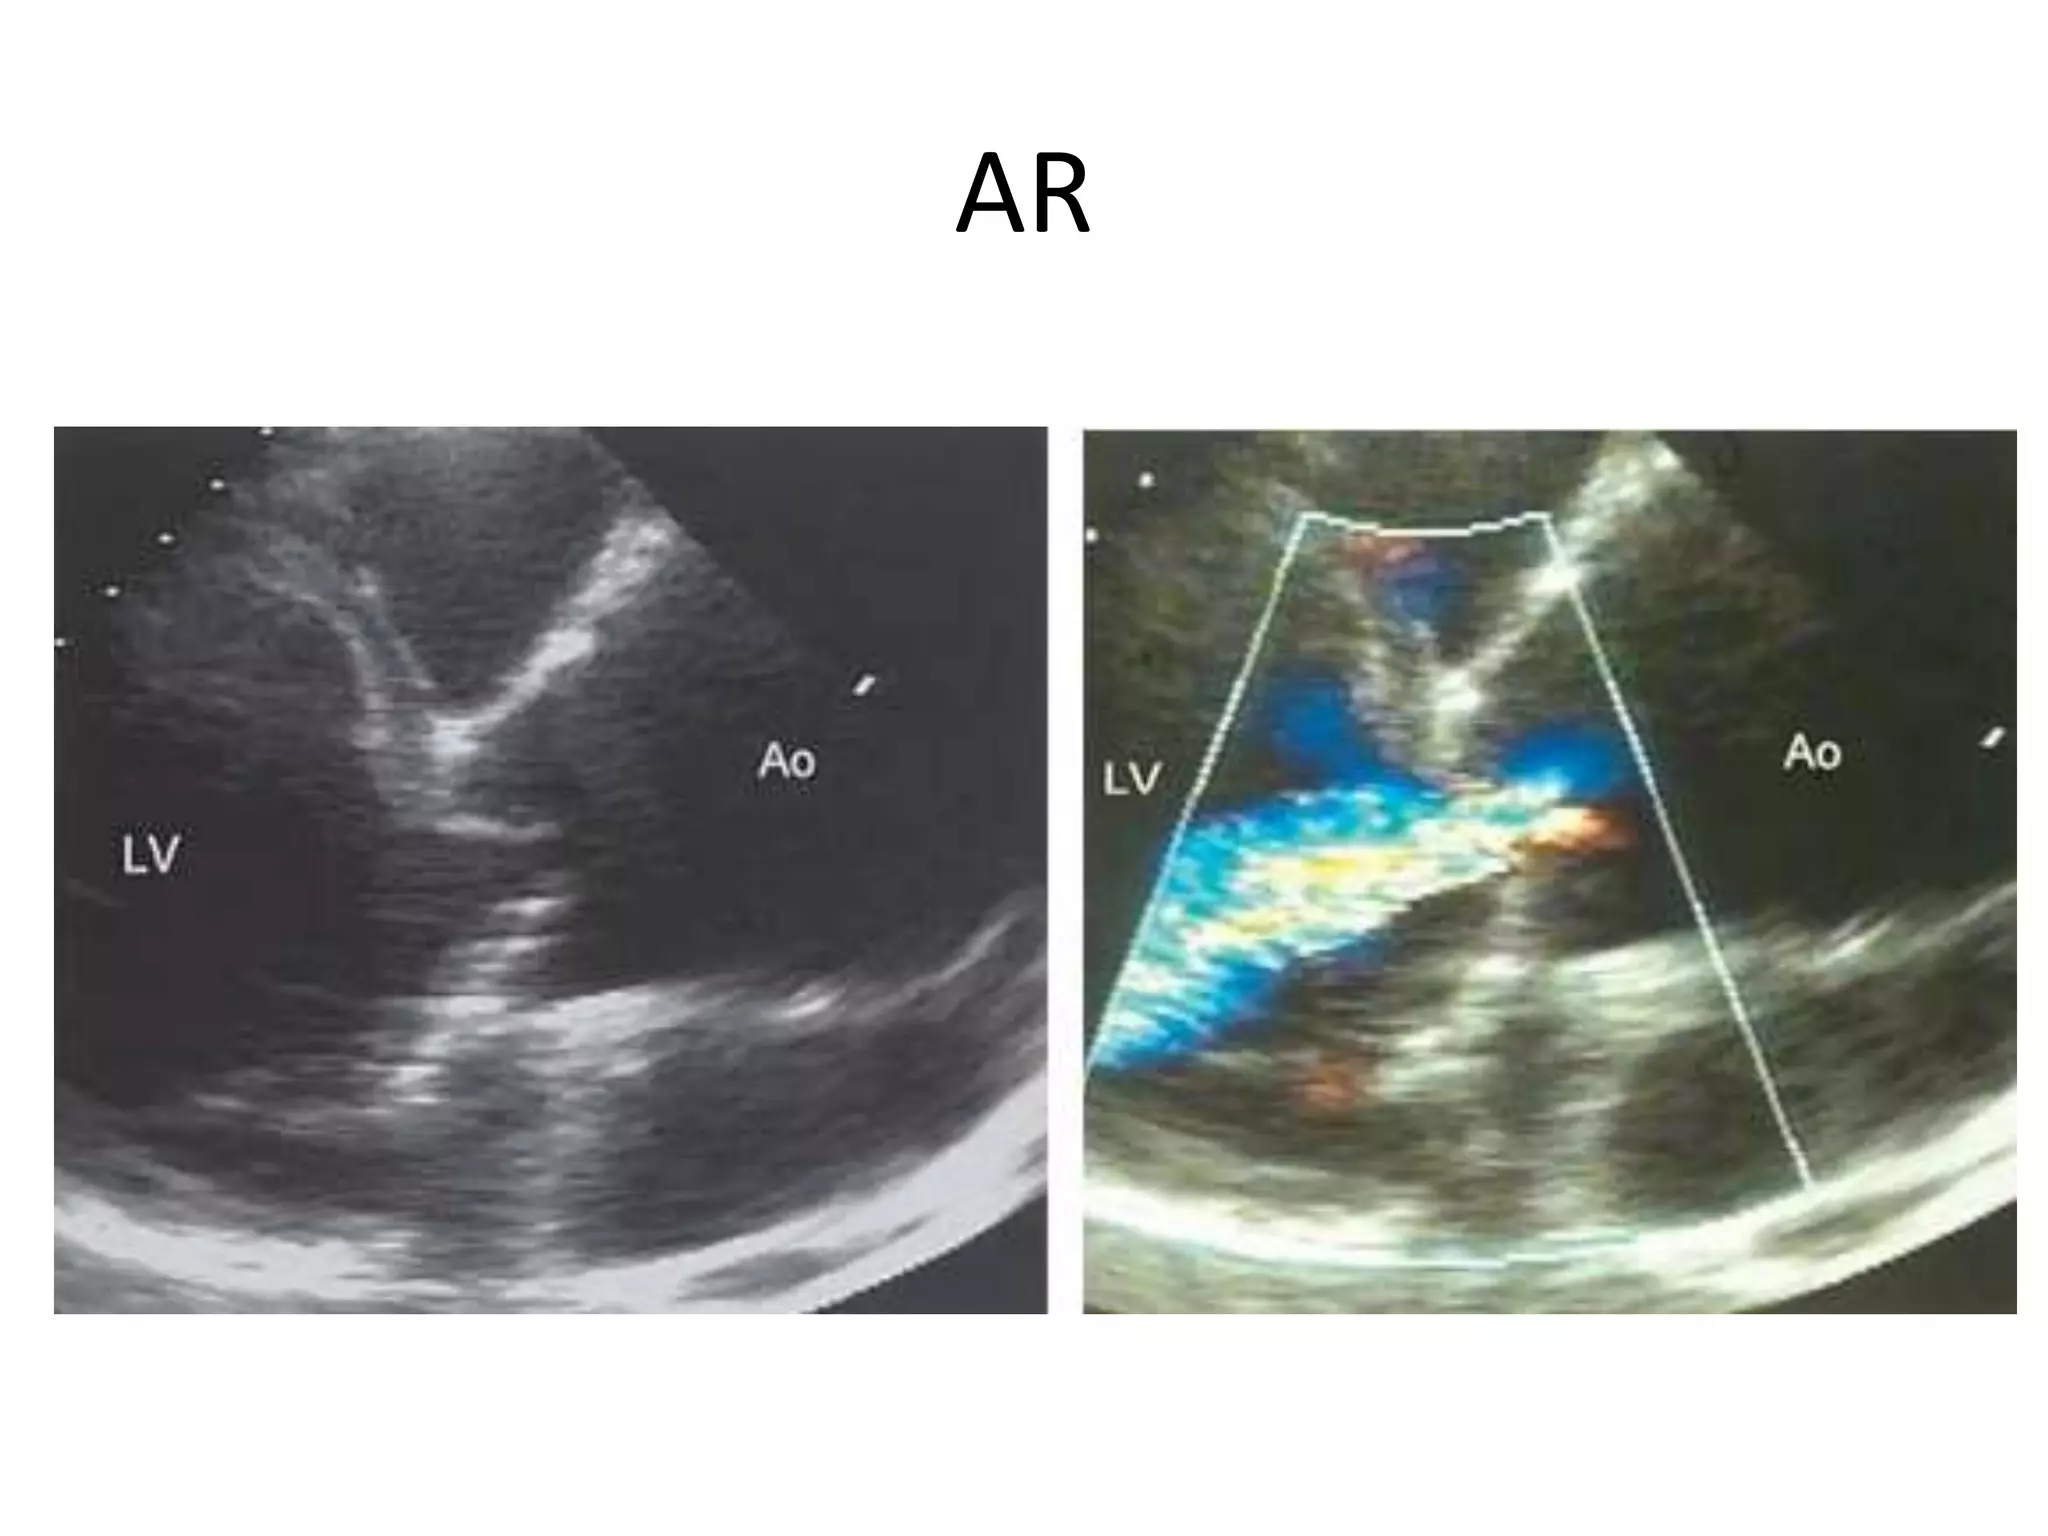

AR